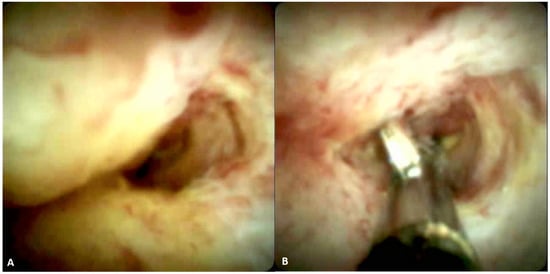

- De Oliveira, P.V.A.G.; De Moura, D.T.H.; Ribeiro, I.B.; Bazarbashi, A.N.; Franzini, T.A.P.; Dos Santos, M.E.L.; Bernardo, W.M.; De Moura, E.G.H. Efficacy of digital single-operator cholangioscopy in the visual interpretation of indeterminate biliary strictures: A systematic review and meta-analysis. Surg. Endosc. 2020, 34, 3321–3329. [Google Scholar] [CrossRef] [PubMed]

- Sethi, A.; Tyberg, A.; Slivka, A.; Adler, D.G.; Desai, A.P.; Sejpal, D.V.; Pleskow, D.K.; Bertani, H.; Gan, S.-I.; Shah, R.; et al. Digital Single-operator Cholangioscopy (DSOC) Improves Interobserver Agreement (IOA) and Accuracy for Evaluation of Indeterminate Biliary Strictures. J. Clin. Gastroenterol. 2020. [Google Scholar] [CrossRef] [PubMed]

- Lee, Y.N.; Moon, J.H.; Choi, H.J.; Kim, H.K.; Lee, H.W.; Lee, T.H.; Choi, M.H.; Cha, S.-W.; Cho, Y.D.; Park, S.-H. Tissue acquisition for diagnosis of biliary strictures using peroral cholangioscopy or endoscopic ultrasound-guided fine-needle aspiration. Endoscopy 2018, 51, 50–59. [Google Scholar] [CrossRef]